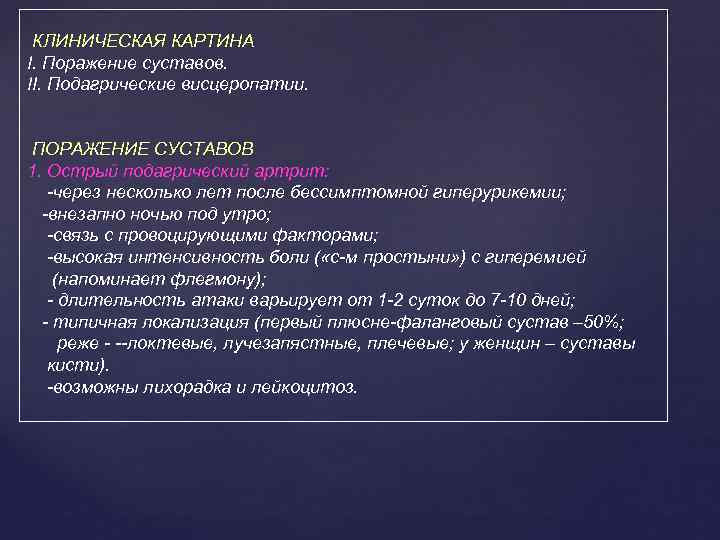

КЛИНИЧЕСКАЯ КАРТИНА I. Поражение суставов. II. Подагрические висцеропатии. ПОРАЖЕНИЕ СУСТАВОВ 1. Острый подагрический артрит: -через несколько лет после бессимптомной гиперурикемии; -внезапно ночью под утро; -связь с провоцирующими факторами; -высокая интенсивность боли ( «с-м простыни» ) с гиперемией (напоминает флегмону); - длительность атаки варьирует от 1 -2 суток до 7 -10 дней; - типичная локализация (первый плюсне-фаланговый сустав – 50%; реже - --локтевые, лучезапястные, плечевые; у женщин – суставы кисти). -возможны лихорадка и лейкоцитоз.

КЛИНИЧЕСКАЯ КАРТИНА I. Поражение суставов. II. Подагрические висцеропатии. ПОРАЖЕНИЕ СУСТАВОВ 1. Острый подагрический артрит: -через несколько лет после бессимптомной гиперурикемии; -внезапно ночью под утро; -связь с провоцирующими факторами; -высокая интенсивность боли ( «с-м простыни» ) с гиперемией (напоминает флегмону); - длительность атаки варьирует от 1 -2 суток до 7 -10 дней; - типичная локализация (первый плюсне-фаланговый сустав – 50%; реже - --локтевые, лучезапястные, плечевые; у женщин – суставы кисти). -возможны лихорадка и лейкоцитоз.